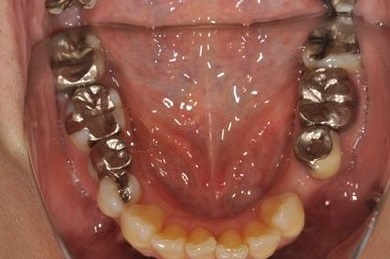

| 性別/年齢 | 女性 / 54歳 | ||||||||||||||||||||||||||||||||

| 主訴 | 下顎の奥歯を抜歯したままになっており、歯茎が少しやせて、両側の歯が少し倒れているような気がする。可能であればインプラントを入れたい。 | ||||||||||||||||||||||||||||||||

| 治療内容 | インプラント1本、メタルボンドセラミック1本 | ||||||||||||||||||||||||||||||||

| 総治療費 | 445,238円 | ||||||||||||||||||||||||||||||||

| 治療期間 | 5ヶ月 |